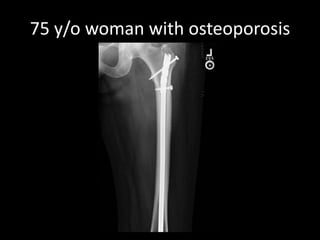

A 52-year-old man underwent a CT FDG PET fused PET/CT scan for a palpable lump. A 40-year-old woman with back pain received MRI scans including STIR, T1, and contrast images. Another patient, a 75-year-old woman with osteoporosis, also received imaging.